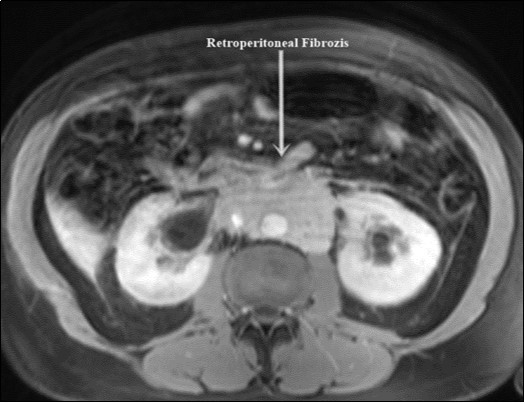

A 58-year-old male patient was admitted to our clinic with complaints of severe weakness, loss of appetite and decreased urine volume. The patient had chronic, mild lower urinary tract symptoms. Serum creatinine level of the patient was 5.3 mg/dl and he had no additional diseases except hypertension. Bilateral grade 3 hydronephrosis and moderate residual urine was revealed in urinary ultrasonography. A transurethral foley catheter was inserted and the patient was admitted to the internal medicine intensive care unit with the diagnosis of acute renal failure due to infravesical obstruction. During follow-up, abdominal magnetic resonance imaging (MRI) was performed due to oliguria and high serum creatinine level (Figure 1). Magnetic resonance imaging revealed a mass of approximately 88x49 mm in the axial plane at the renal artery outlet level, consistent with retroperitoneal fibrosis, tuberculous lymphadenitis or lymphoma. Grade 3 pelvicaliectasis was seen in bilateral kidneys. The descripted lesion was observed in paraaortic area (except posterior). Tru-cut biopsy was planned with no evidence of malignancy on positron emission tomography. Tru-cut biopsy reported as connective tissue. Bilateral double-J ureteral stent was placed endoscopically to patient who was diagnosed as idiopathic retroperitoneal fibrosis (Figure 2). At the same time, alpha-blocker treatment was started. Creatinine levels decreased to normal after five days and normal volume voiding was observed after removal of foley catheter. The patient was started on glucocorticoid therapy which was foreseen to last for 1 year. After 2 months, PET imaging showed the decreased mass size and metabolic activity. Thereafter bilateral ureteral double-J stents were removed endoscopically. Ultrasonographic imaging showed no hydronephrosis after 7 days of catheter removal and the patient was recommended to continue glucocorticoid therapy and was followed up.

Figure 1.Retroperitoneal fibrosis involving both ureters.

Retroperitoneal fibrosis involving both ureters.